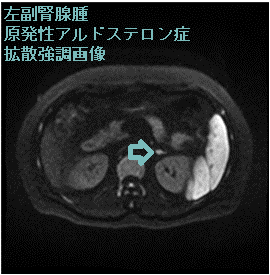

2cm以下の小さいものがほとんどで、超音波検査やCTで見つかりにくい難点があります。両側過形成腺腫・非機能性腺腫の合併が多いです。

副腎腫瘍による原発性アルドステロン症は高血圧の15%だが本態性高血圧と間違えられ治療されている。心血管障害が多く予後不良。超音波検査やCTで見つかりにくい、普通の降圧薬が効きにくい、血圧変動激しい、ノンディパー型、低カリウム血症(カリウム正常の方が多い)で筋力低下、脱力発作、不整脈、腎性尿崩症、血圧下がってもアルドステロンそのもので動脈硬化が進行し脳卒中・心筋梗塞・心房細動。血漿アルドステロン濃度/血漿レニン活性比、カプトプリル負荷試験などで診断。治療は腹腔鏡下手術、スピロノラクトン(アルダクトンA)・エプレレノン(セララ)・エサキセレノン(ミネブロ)。